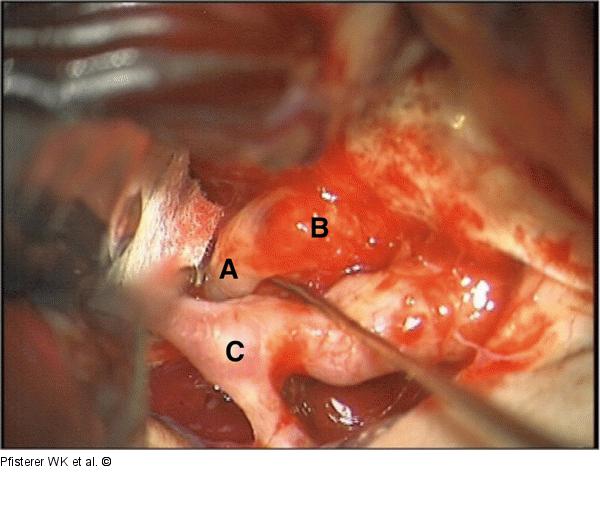

Abbildung 1: Intraoperativer Situs Intraoperativer Situs Patient 2 A: N. oculomotorius, B: Meningeom, C: Carotisbifurkation |

Abbildung 1: Intraoperativer Situs

Intraoperativer Situs Patient 2 A: N. oculomotorius, B: Meningeom, C: Carotisbifurkation |